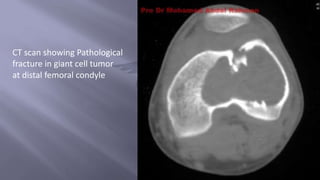

 CT scans:

-Most sensitive for detecting bone destruction

-Determines extent of cortical involvement

-Also used to search for primary lesion in pelvis, abdomen or chest

CT scan showing Pathological

fracture in giant cell tumor

at distal femoral condyle

 CT scans: -Mostsensitive for detecting bone destruction -Determines extent of cortical involvement -Also used to search for primary lesion in pelvis, abdomen or chest

CT scan showingPathological fracture in giant cell tumor at distal femoral condyle